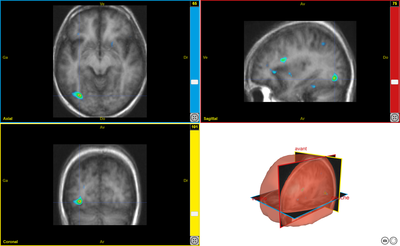

scenar8

Image dans sa taille originale :

Ancien logiciel : EduAnatomist et Neuropeda

Informations sur les images AnaPeda

Exemple de lien direct vers EduAnat 2 en ligne